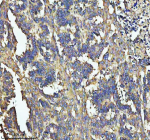

Immunohistochemical staining of SOS1 using anti-SOS1 antibody. SOS1 was detected in a paraffin-embedded section of human colon cancer tissue. Heat mediated antigen retrieval was performed in EDTA buffer (pH 8.0, epitope retrieval solution). The tissue section was blocked with 10% goat serum. The tissue section was then incubated with 2 ug/ml rabbit anti-SOS1 antibody overnight at 4oC. Peroxidase Conjugated Goat Anti-rabbit IgG was used as secondary antibody and incubated for 30 minutes at 37oC. The tissue section was developed using an HRP secondary and DAB substrate.